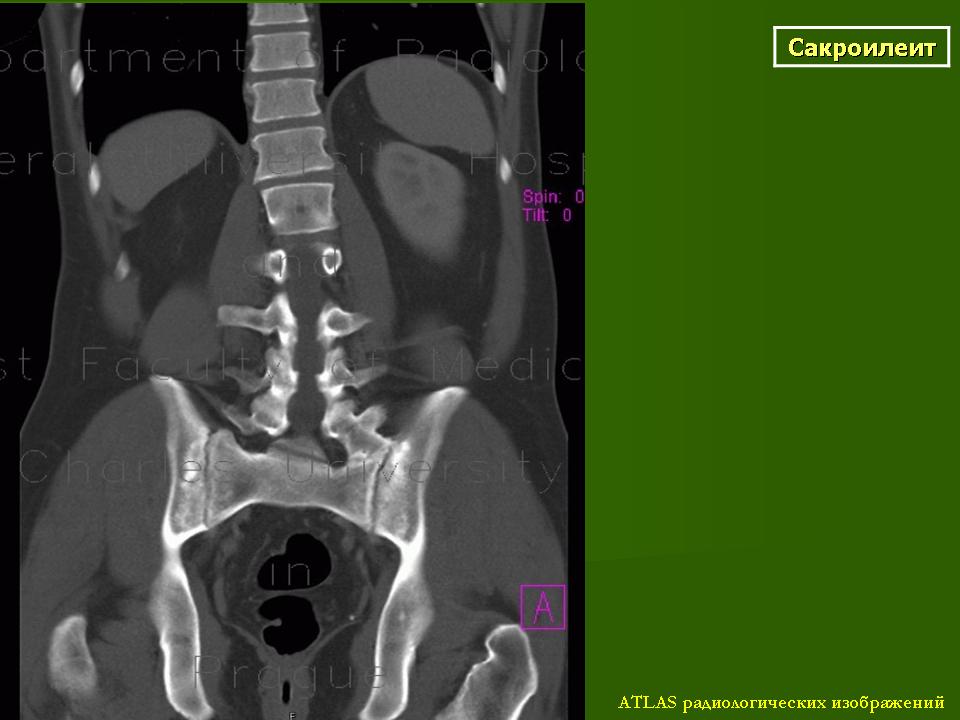

КТ КПС в аксиальной (а) и корональной (b) проекциях, 3D реконструкции (c, d): двусторонний сакроилиит IV стадии – полный костный анкилоз + анкилоз межпозвонковых суставов, оссификация передней продольной связки по типу «бамбуковой палки». http://congress-ph.ru/common/htdocs/upload/fm/rar/17/prez/A-10-02.pdf